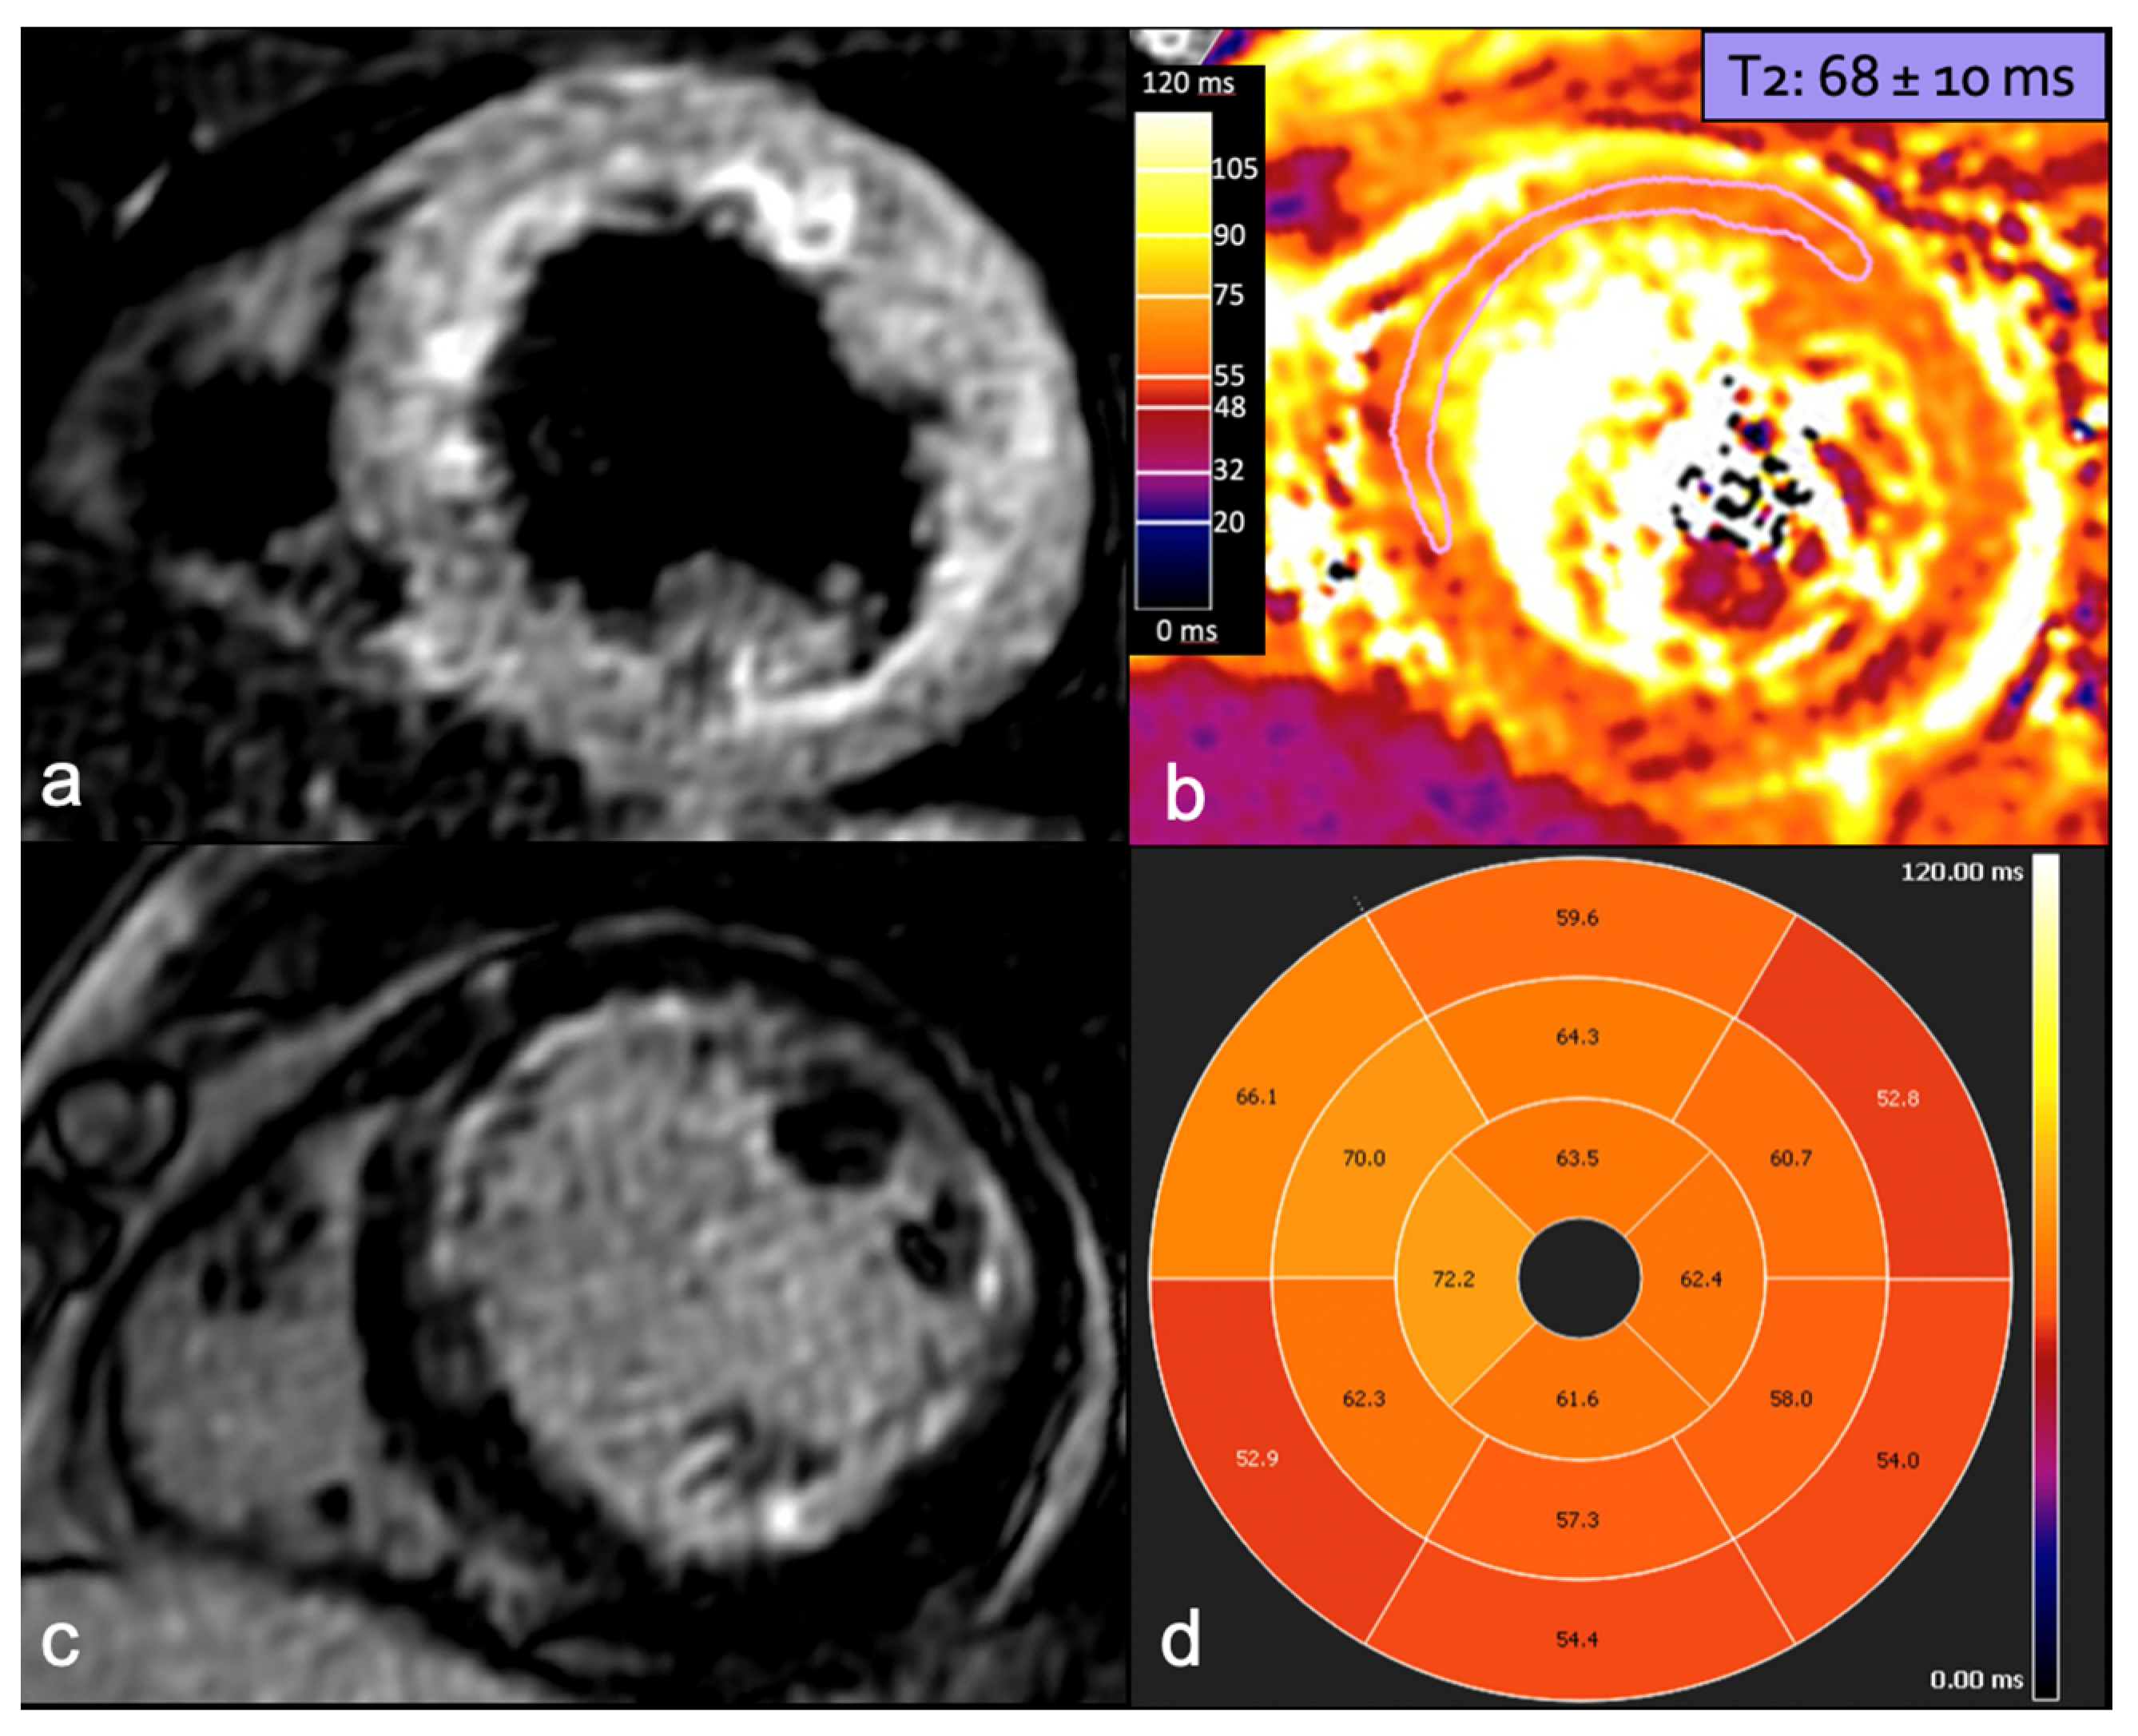

Figure 6.

A 36-year-old woman at week 36 of pregnancy presented with chest pain and anterior ST-segment elevation on ECG. CMR detected edema in the LAD territory in STIR sequence (a), confirmed by increased T2 mapping values in the same territory, with maximum values in the mid-ventricular anterior and anteroseptal segments (b,d), consistent with recent infarction-related changes. LGE with ischemic subendocardial pattern in LAD territory is depicted in delayed-enhancement sequence (c). CMR: cardiac magnetic resonance; LAD: left anterior descending artery; STIR: short tau inversion recovery; and LGE: late gadolinium enhancement.

Finally, the implementation of quantitative T1- and T2-mapping techniques has significantly enhanced the accuracy of detecting myocardial edema and scar tissue, providing valuable insights into the extent of cardiac damage and aiding in the assessment of myocardial viability.